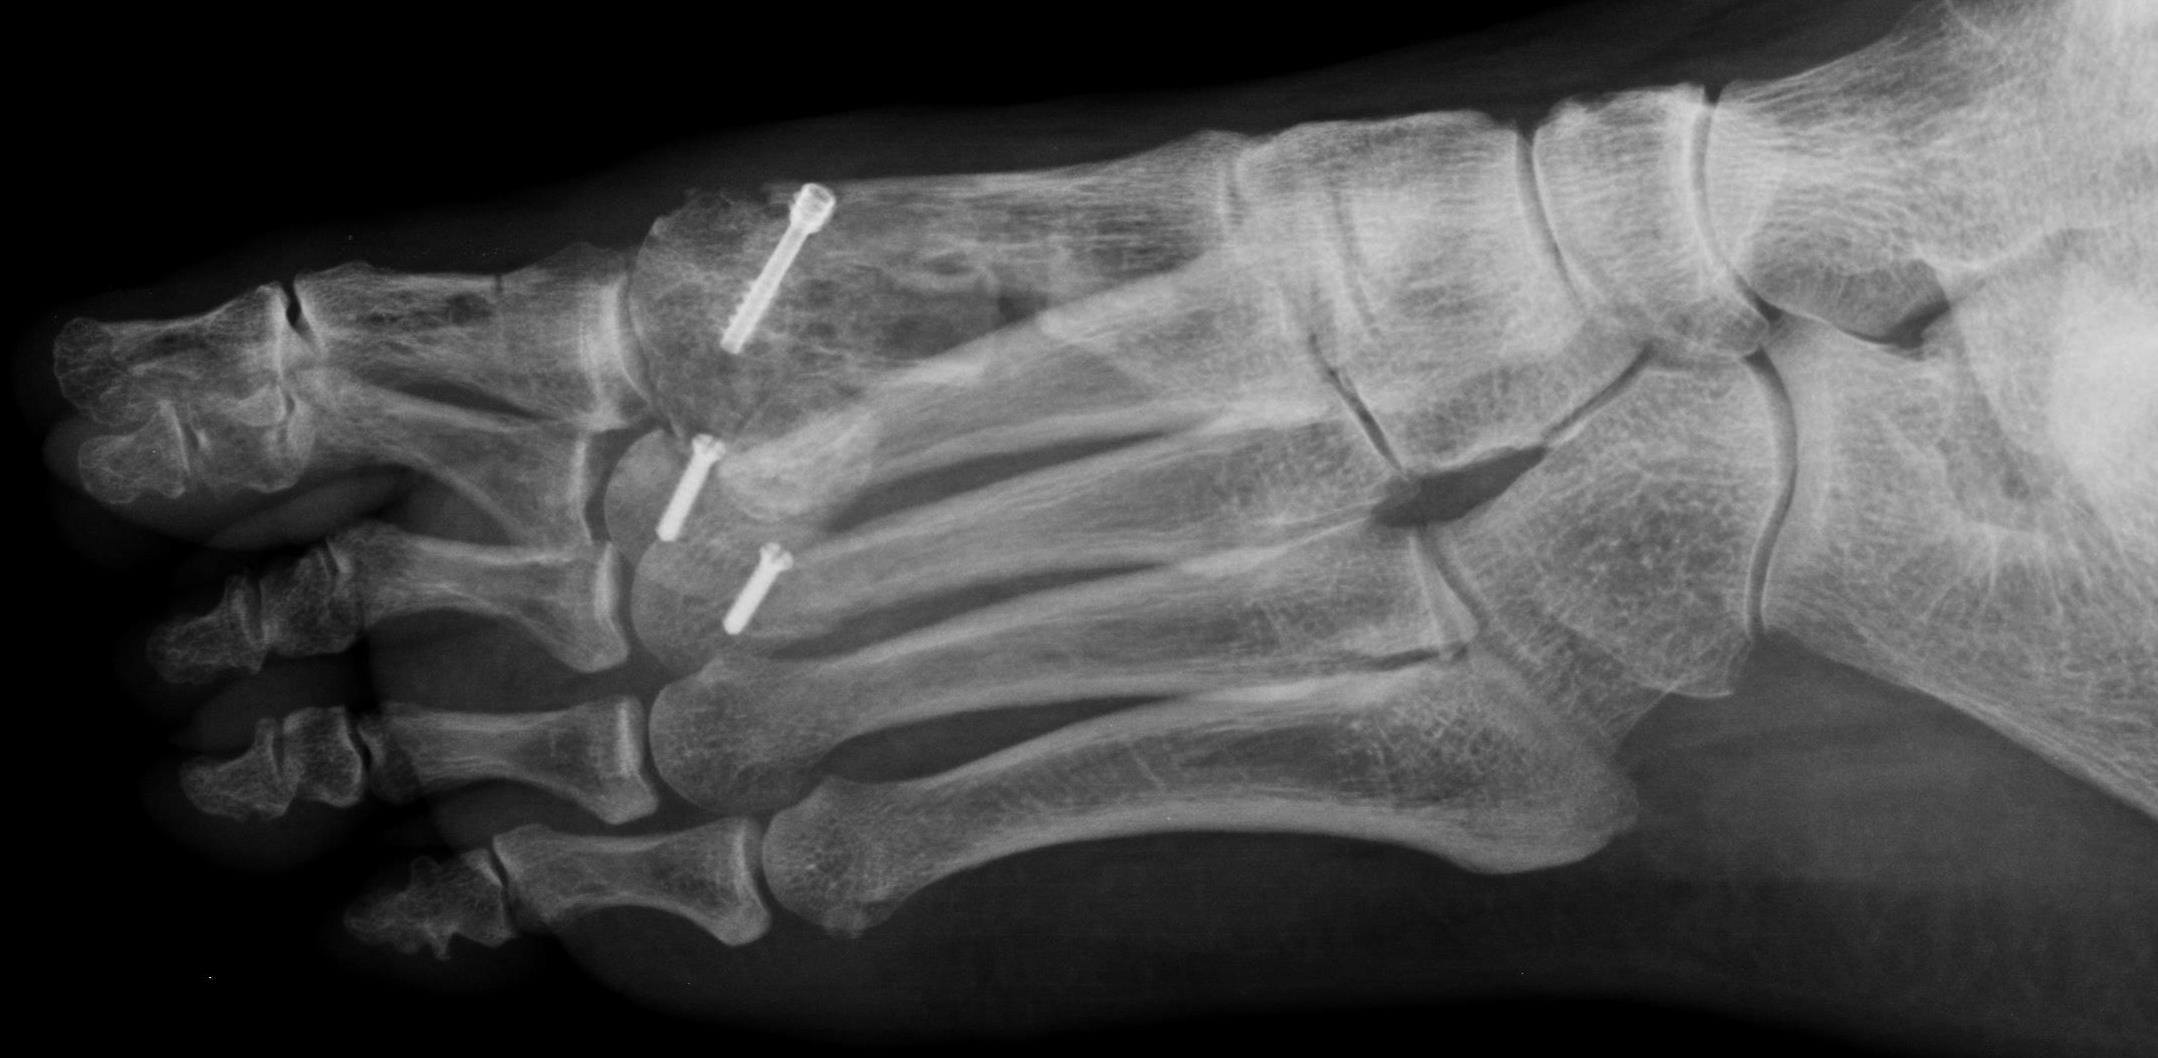

W zależności od rodzaju deformacji, stosuje się różne rodzaje osteotomii (przecięcia) kości śródstopia, co ma przywrócić obecność prawidłowego łuku poprzecznego stopy. Leczenie operacyjne płaskostopia poprzecznego można wykonać metodami klasycznymi. W tej grupie najpopularniejsze są osteotomie Weil. U pewnej grupy Pacjentów leczenie można też prowadzić metodami miniinwazyjnymi – tj. za pomocą niewielkich (0,5 cm) nacięć skóry. W tej grupie znajdują się między innymi osteotomie DMMO. Każda z podanych grup metod ma swoje wady i zalety, a ich odpowiedni dobór zależy od wiedzy i doświadczenia chirurga stopy.